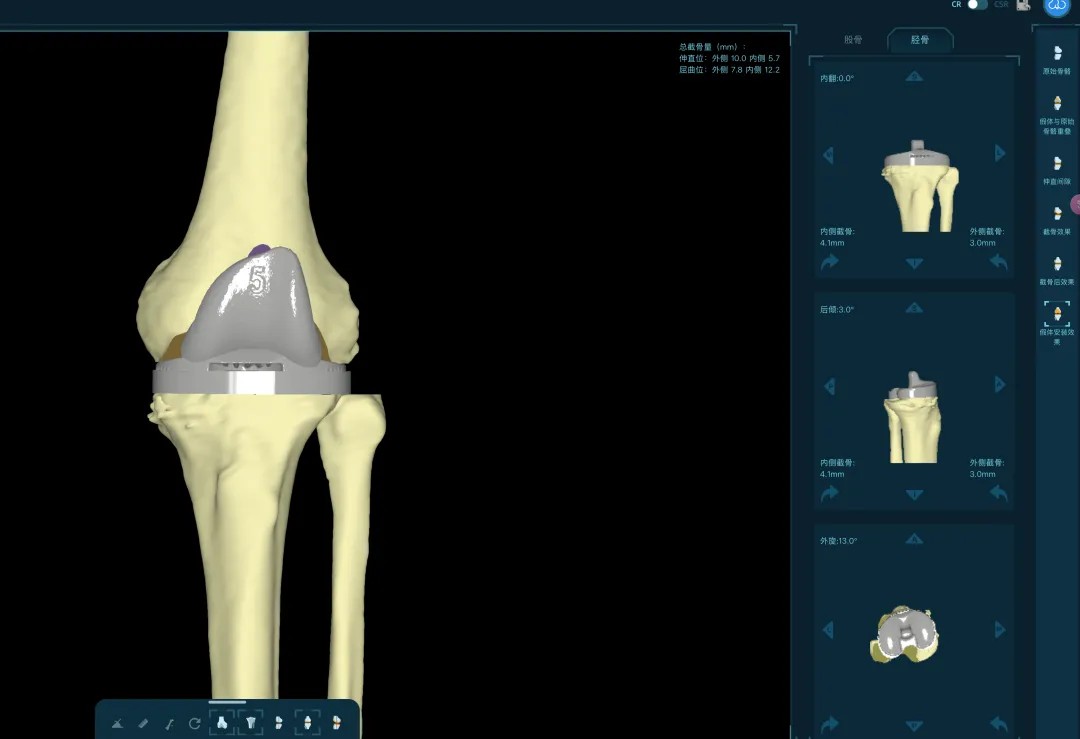

清創(chuàng)只是第一步,如何在一片“復(fù)雜地形”中重建一個(gè)穩(wěn)定、功能良好的膝關(guān)節(jié),是更大的挑戰(zhàn)。為此,團(tuán)隊(duì)引入了計(jì)算機(jī)輔助手術(shù)規(guī)劃系統(tǒng)。

通過患者的CT數(shù)據(jù),系統(tǒng)構(gòu)建出膝關(guān)節(jié)的三維數(shù)字模型,精確評(píng)估骨缺損的范圍與形態(tài)。醫(yī)生可以在虛擬空間中,提前模擬手術(shù)過程,為患者“量體裁衣”,規(guī)劃出假體安放的最佳位置、角度以及所需填充骨缺損的特殊墊塊型號(hào)。

“這相當(dāng)于在真實(shí)戰(zhàn)斗前,進(jìn)行了一次全方位的沙盤推演。”羅軍介紹,這種規(guī)劃確保了手術(shù)的精準(zhǔn)度,縮短了手術(shù)時(shí)間,也為使用先進(jìn)的翻修假體系統(tǒng)做好了完美鋪墊。

本次手術(shù)的核心,是采用了Evolution® ECCK膝關(guān)節(jié)翻修系統(tǒng)。該系統(tǒng)專為應(yīng)對(duì)翻修手術(shù)中常見的嚴(yán)重骨缺損、韌帶功能不全等極端復(fù)雜情況而設(shè)計(jì)。

其模塊化的組件提供了前所未有的靈活性,就像一套高精度的“工程套件”,允許醫(yī)生在術(shù)中根據(jù)實(shí)際骨缺損情況,自由組合不同尺寸的墊塊、延長桿等部件,實(shí)現(xiàn)關(guān)節(jié)線和力學(xué)穩(wěn)定性的個(gè)體化重建。